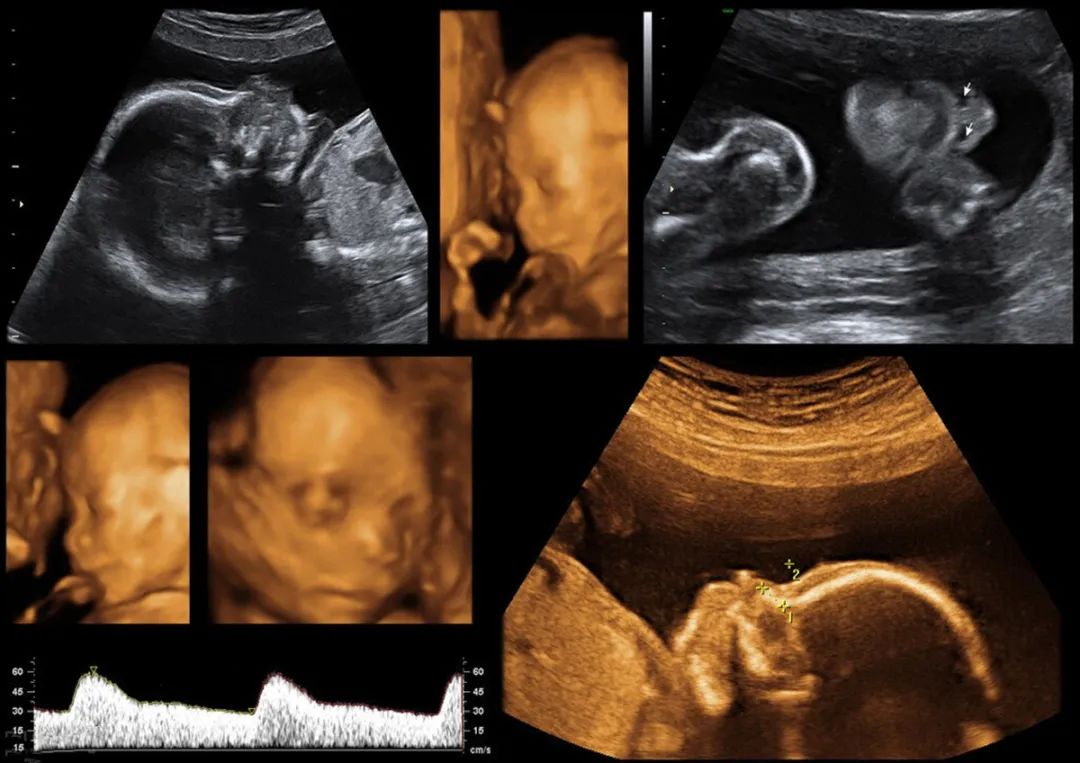

四维排畸检查

四维排畸这项检查 , 通常到孕中期 , 医生都会建议做去做 , 一旦孩子身上有残缺畸形 , 就可以提前知道 。

可是很多人却认为 , 所谓的四维排畸和B超没有太大的区别 , 所以 , 就觉得四维排畸检查是浪费钱 , 很没有必要去做 。

殊不知 , 就因为自己的无知 , 结果害惨了娃 , 让孩子一出生就被别人“贴标签” 。 为了让娃将来少受罪 , 孕期这项检查不能落下 。